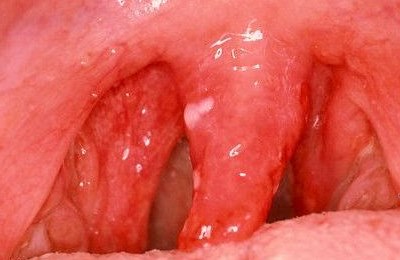

Хронический атрофический и гипертрофический фарингиты отличаются картиной при фарингоскопии, а также наличием при гипертрофической форме жалоб на обильное отделение слизи, зачастую с прожилками гноя.

Так, при грибковом фарингите обнаруживается жёлтоватый или беловатый налёт, при атрофическом – признаки истончения и склерозирования, при гипертрофическом возможно обнаружение утолщения слизистой оболочки, а также появление разнообразных узелков.